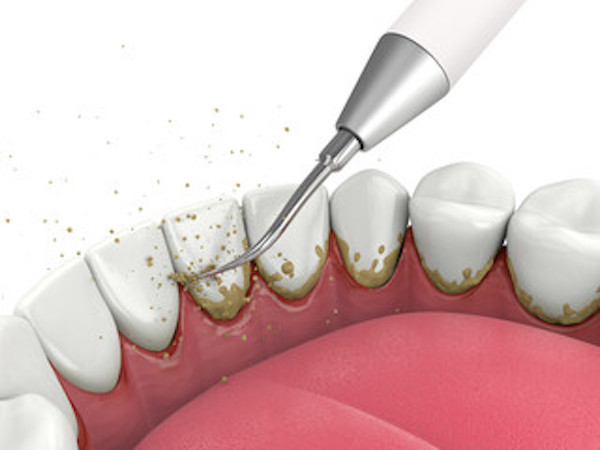

・スケーリング

スケーラーと呼ばれる器具を使用して、歯と歯の間や歯茎の上についている歯石(縁上歯石)を除去します。

・ルートプレーニング

歯茎の中や歯根表面にこびりついている歯石(縁下歯石)を除去し、歯根表面を滑らかに研磨して再び汚れがつきにくいようにします。